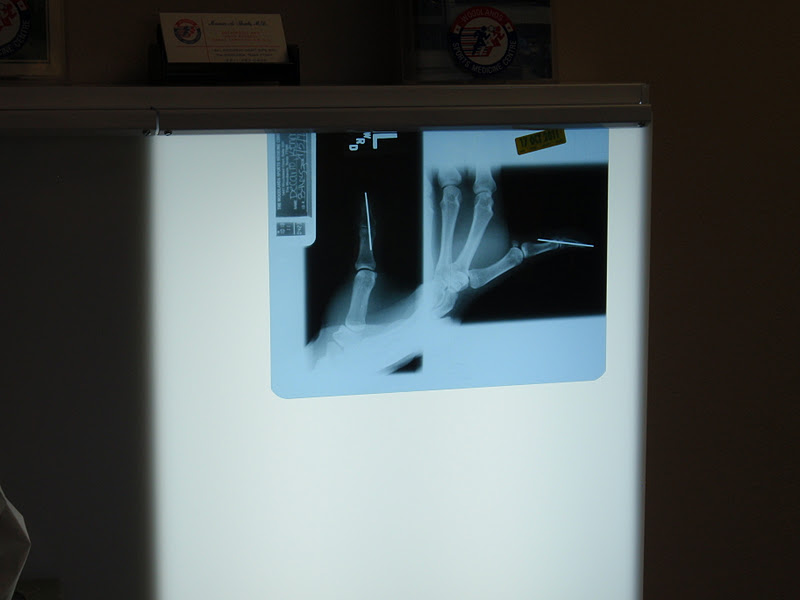

The appointment began with another x-ray to check the location of the pin.  A good idea since Randy has been hammering it in with various hard surfaces throughout the past 6 weeks.  Looks kind of freaky, doesn't it?